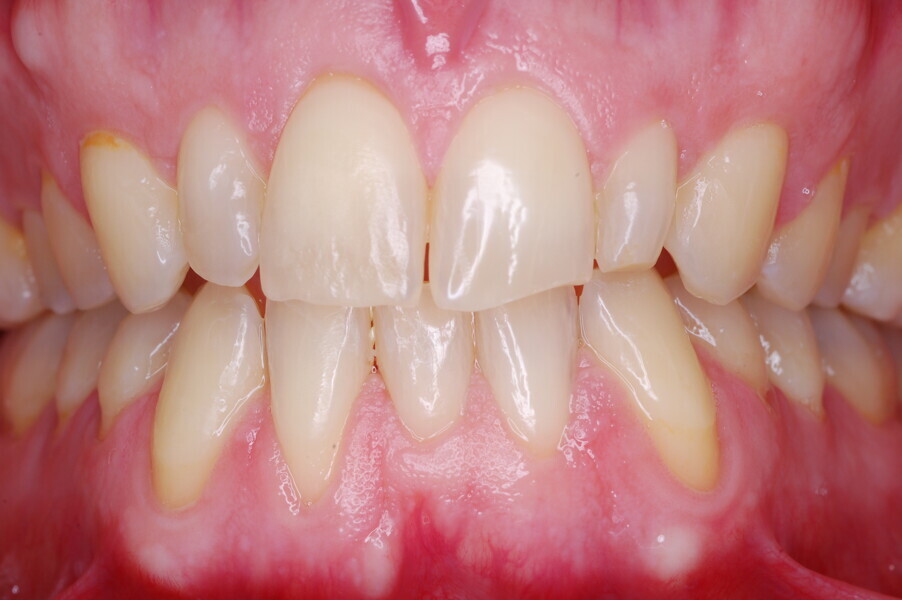

A healthy 39-year-old man presented to our orthodontic office with the chief complaint of an unattractive dental appearance and fear of the orthognathic surgery proposed by another orthodontist. Clinically, the patient’s profile was straight, and the frontal view did not show any facial asymmetry. The functional examination did not reveal any mandibular deviation or reduced movements. The patient had no joint pain, and no joint noise was observed.

Figs. 1–8: Pretreatment facial and intra-oral photographs.

From the periodontal point of view, the patient showed a good attitude to oral hygiene, but crowding of the mandibular incisors made cleaning difficult in that area, causing plaque accumulation and localised gingival inflammation. The panoramic radiograph revealed the presence of the mandibular third molars and confirmed the absence of the mandibular right central incisor (Fig. 10).

The cephalometric analysis showed a skeletal Class II malocclusion (convexity of Point A: 4.9 mm), a slightly retruded chin position (facial depth: 78.1°) and a skeletal open bite tendency (lower facial height: 53.19°; facial axis: 80.58°; Fig. 9). The mandibular incisors were lingually tipped (Li–APog: 9.3°) and retruded (Li–APog: 1.55 mm), and there was an increased inter-incisal angle of 142.9°.